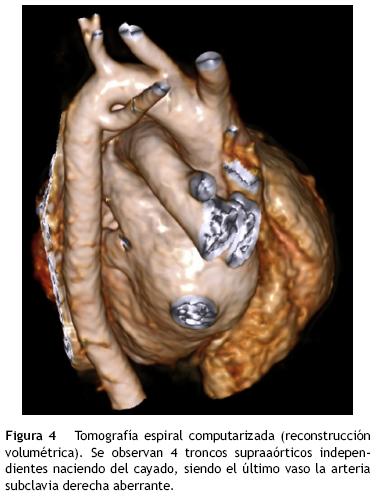

En una reconstrucción volumétrica se observaba el nacimiento independiente de los 4 troncos, siendo la arteria subclavia derecha aberrante el último vaso que emerge del arco. Este vaso aberrante nace del segmento posteroinferior del arco aórtico distal y cruza hacia el lado derecho posterior a la tráquea (fig. 4).